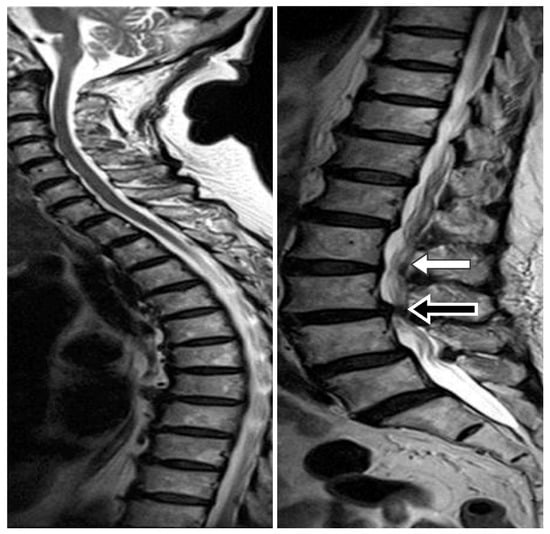

- It avoided the kinking of the lumbar spinal catheter in the thecal sac. In our experience, spinal catheter entanglement or twisting occurred in about 10%–15% cases, but we were able to correct it immediately under fluoroscopic guidance (Figure 5).

- It ensured the level of the lumbar catheter tip placement. We placed the spinal catheter tip at the T8–10 level, which helped to avoid extraction of the spinal catheter from thecal sac when the patient performs strenuous exercise. Matsubara et al. revealed a case report of CSF leakage into the epidural space through a side hole, due to placement of a length of the spinal catheter into the dural sac. Shortly after the operation, the side hole was opened up when the patient moved his body [15].